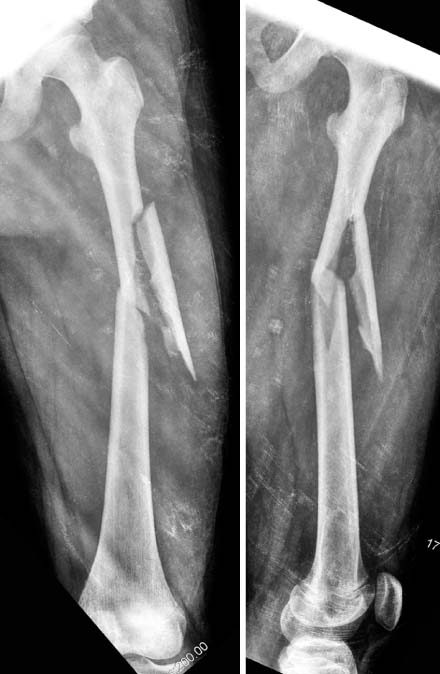

Fig. 1

A femoral shaft fracture with a butterfly fragment in 11 years-old girl.

Fig. 1 A femoral shaft fracture with a butterfly fragment in 11 years-old girl.